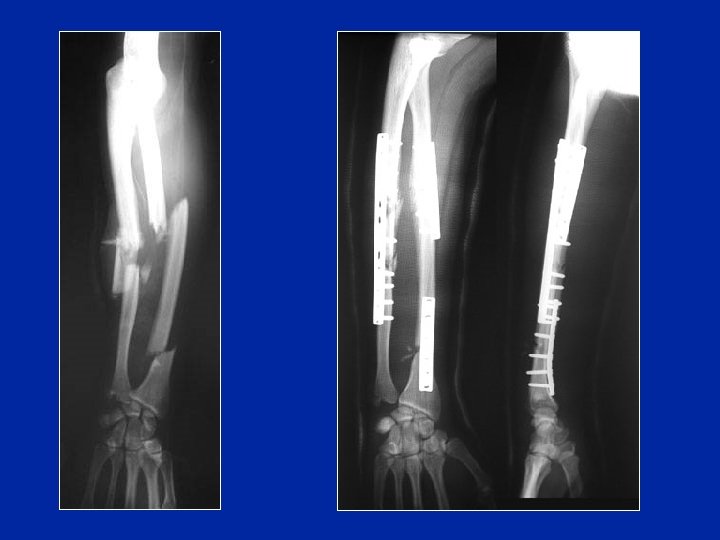

Traitement chirurgical Fractures irréductibles de l’enfant Fractures déplacées de l’adulte Mobilisation rapide Consolidation en 3 mois

Déplacement sous plâtre ostéosynthèse par plaques

Ostéosynthèse des 2 os au tiers distal chez un enfant Interposition musculaire